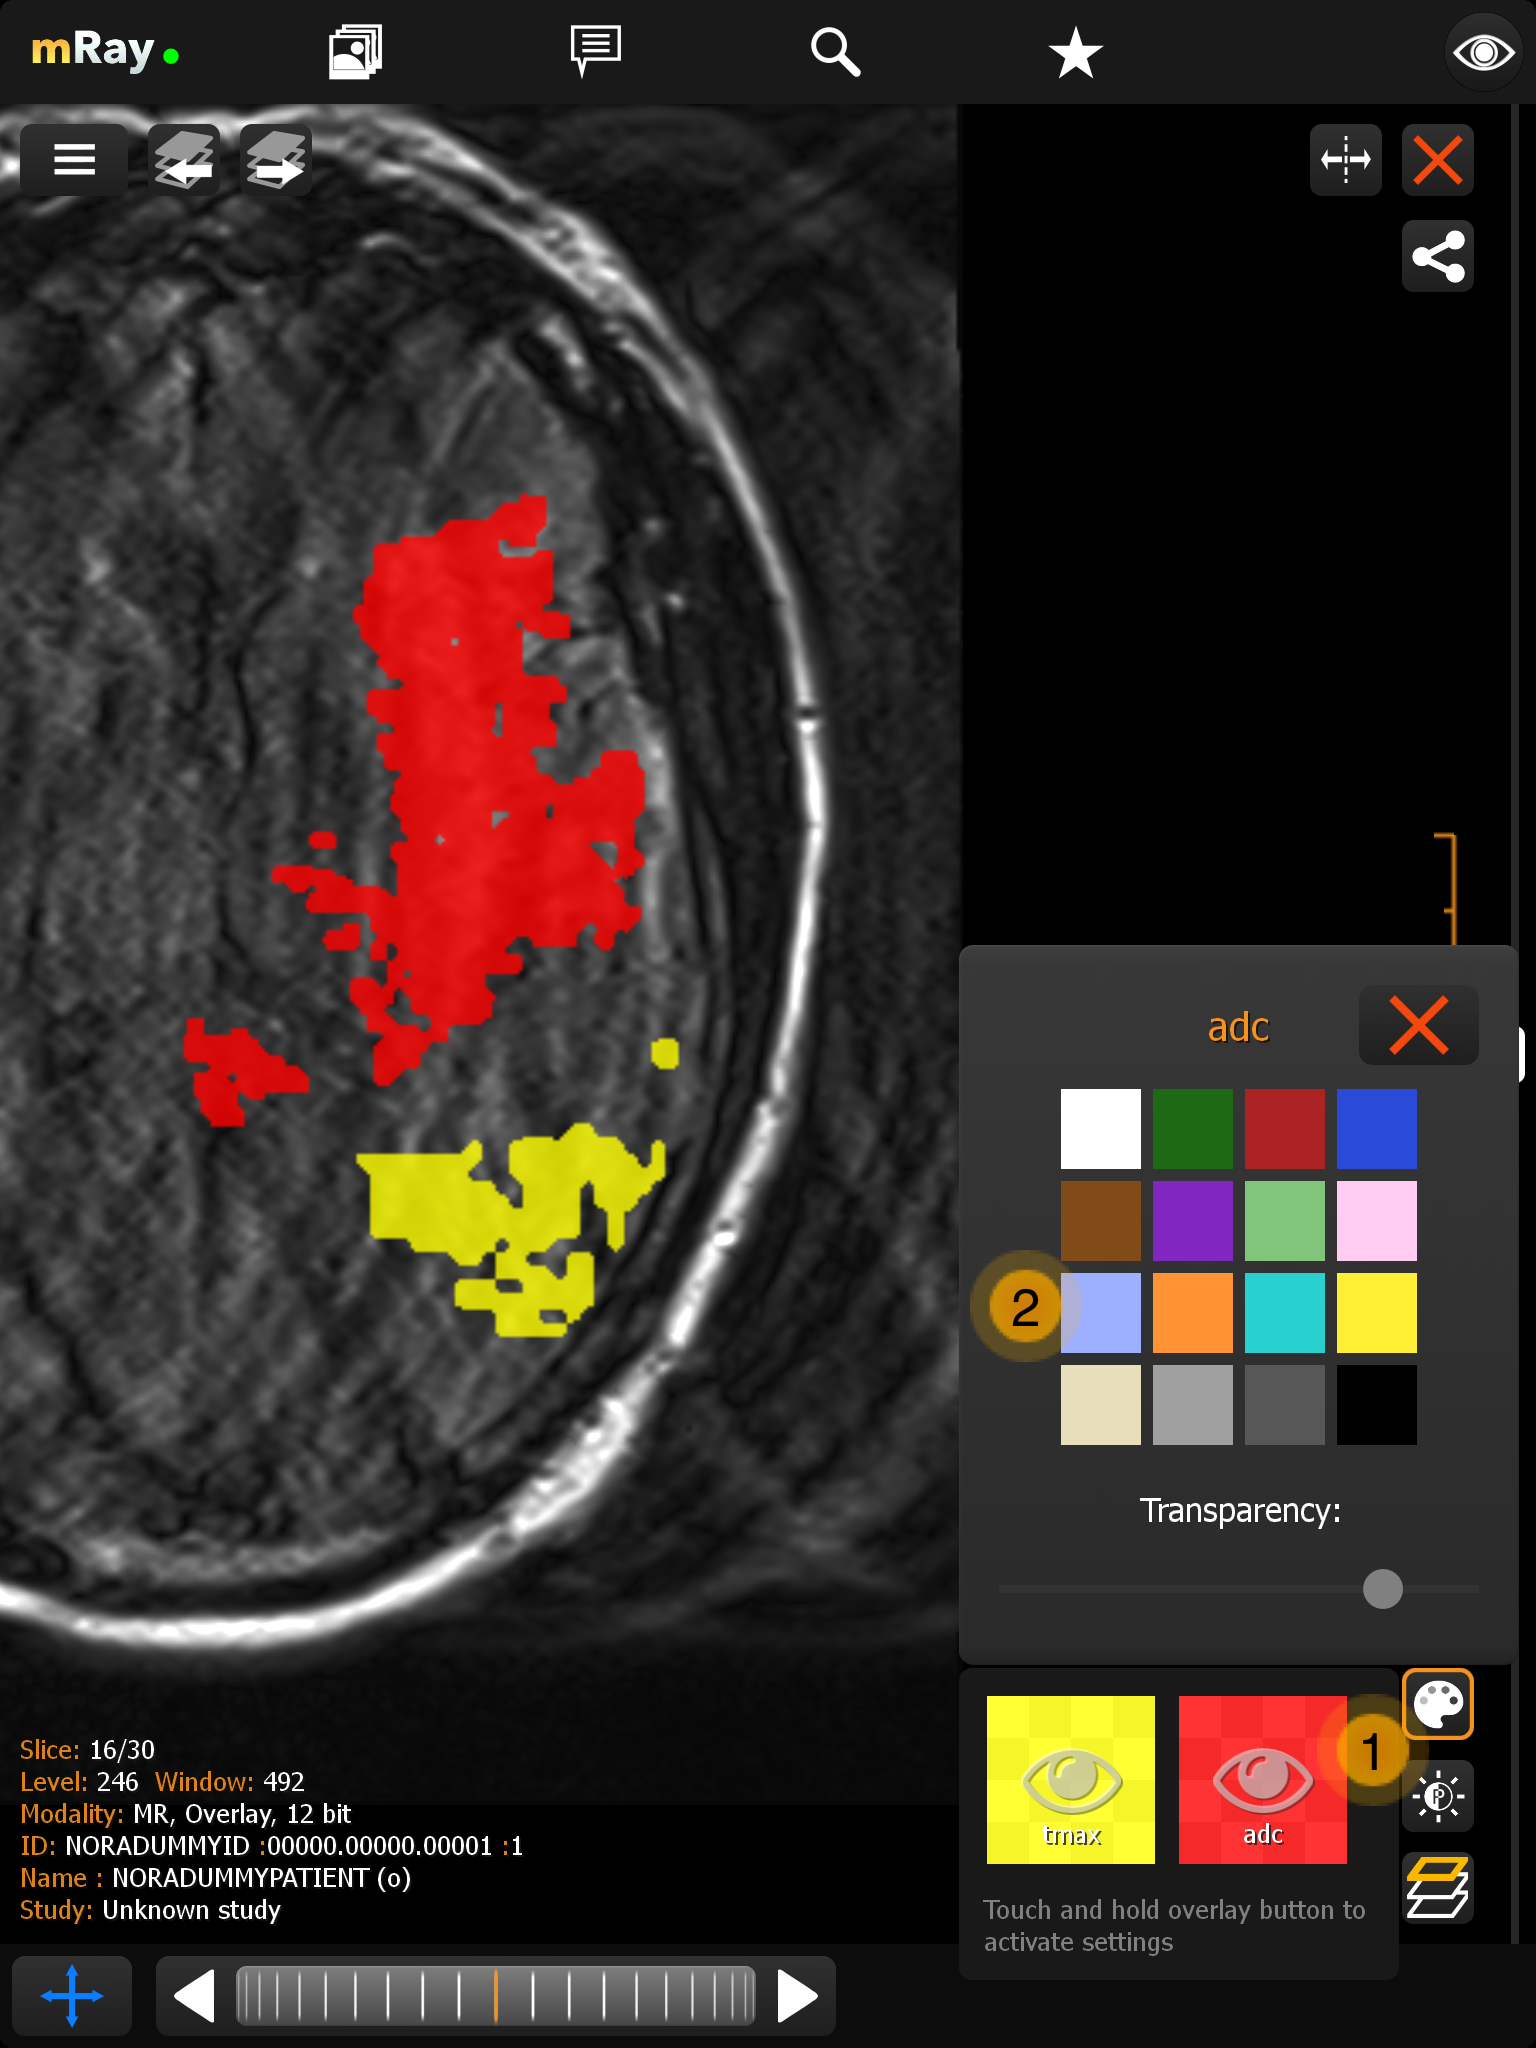

11.2. Overlay menu

mRay supports the display of DICOM files with up to 16 overlay masks. These overlays can be switched on and off separately via a menu in the viewer. It is also possible to assign a freely selectable color and transparency to each overlay.

-

Displays the overlay with color and label information. With one click you can switch the respective overlay on or off. To adjust the color and transparency, press and hold the button for a short time.

-

Here you can set the color and transparency for the overlay.